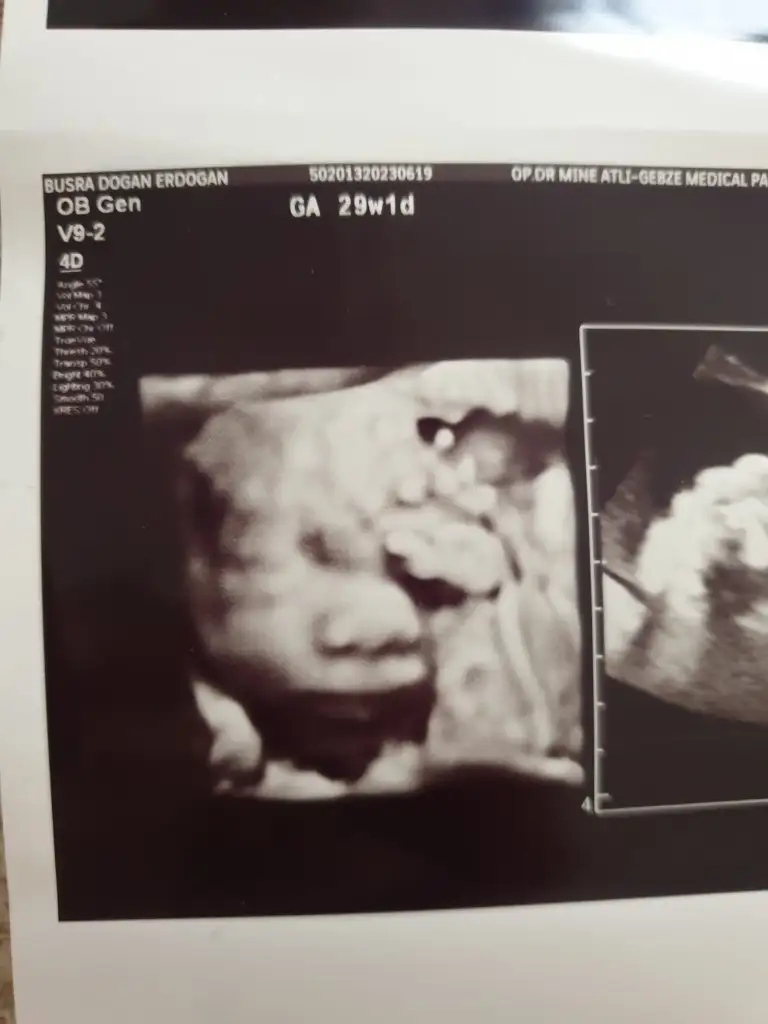

Sonbahardagel Sonbahardagel Z zerdecalim Teach_Mavi Teach_Mavi Melikeben Melikeben dr alttan bakti bi suruntu aldi akinti bu dedi dönemsel olabilir diyerek fitil verdi 1 hafta sonra tekrar gelmemi istedi cok sagolun kizlar dun gece gece aksiyon yasadik bebek suyu gayet yerindeymis 1.350 gr 38 cm olmus 🙏🙏🙏🙏

Eklentiler

• IMG-20230619-WA0002.webp

IMG-20230619-WA0002.webp

10,1 KB · Görüntüleme: 74

• 20230619_144052.webp

20230619_144052.webp

16,1 KB · Görüntüleme: 83